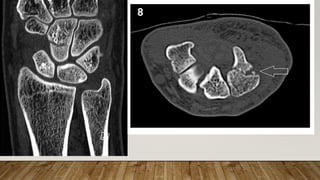

This document discusses radiology and the use of x-rays. It begins with an introduction to radiology and x-rays, noting their importance as the "father of medical investigations." It then discusses anatomy as seen on radiographs and whether x-rays are enough. The document goes on to compare gross views to radiological views, noting what each can and cannot show. It highlights important figures in the development of radiology, from x-rays to CT, MRI, and ultrasound. Specific anatomical structures visible on upper and lower limb x-rays are listed. The document concludes by discussing how pathologies appear on x-rays and the importance of clinical history and knowledge when interpreting radiological images.